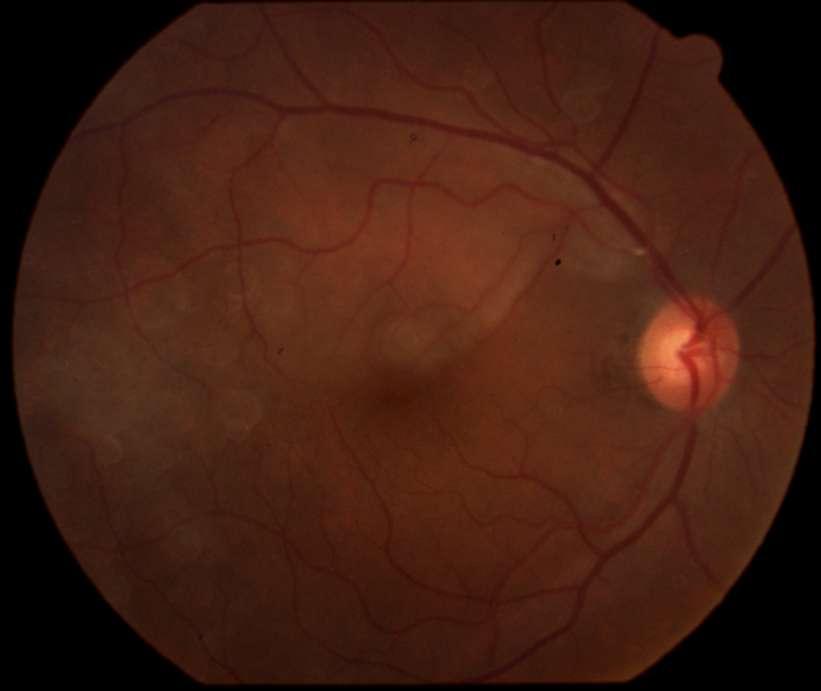

Imágenes aportadas por Dr. Cristian Sánchez

ü La degeneración macular relacionada a la edad es la causa más frecuente de pérdida de visión irreversible en personas mayores de 60 años

ü La patogenia es multifactorial, en que además del envejecimiento (principal factor de riesgo) los factores de riesgo genéticos y ambientales (Tabaquismo, obesidad abdominal) juegan un rol determinante

ü Su primera manifestación son las drusas sin embargo el proceso puede evolucionar a la forma seca o húmeda

ü La forma húmeda se caracteriza por la presencia de membrana neovascular coroidea que crece bajo el epitelio pigmentario y luego bajo la retina. Estos vasos de neoformación se originan en la coriocapilar, proliferan y penetran al espacio subepitelial a través de una ruptura de la membrana de Bruch

ü El desprendimiento de epitelio pigmentario puede preceder la neovascularización coroidea, y en ese caso su contenido es seroso, cuando se asocia a neovascularización coroidea su contenido es fibrovascular

ü Al examen oftalmoscópico, en caso de tener una membrana neovascular, se detecta un solevantamiento retinal, habitualmente redondeado y generalmente rodeado de un halo de sangre subretinal. El solevantamiento se debe a la presencia de líquido o edema retinal. La membrana neovascular puede ser extrafoveal, alejada del centro, pero en la mayoría de los casos es subfoveal

ü Una complicación inusual es la hemorragia subretinal masiva, lo que en algunos pacientes se asocia a terapia anticoagulante

ü Angiografía con fluoresceína en la membrana MNVC Tipo Ia (DEP fibrovascular): se caracteriza por presentar área hiperfluorescente irregular visible desde un tiempo arteriovenoso precoz que incrementa la fluoresceina en tiempos tardíos con poca o nula difusión

2.G. MEMBRANA NEOVASCULAR COROIDEA (MNVC)

Clement F . “Angiografía”. Diagnóstico por la imagen en la retina, Sociedad Española de Retina y Vítreo, editado por Ignasi Jügens, Elservier, 2014, pp 41-66 Juan Verdaguer, T. (2010). Degeneración macular relacionada a la edad. Revista Médica Clínica Las Condes, 21(6), 949–955. doi:10.1016/s0716-8640(10)70620-9

A B